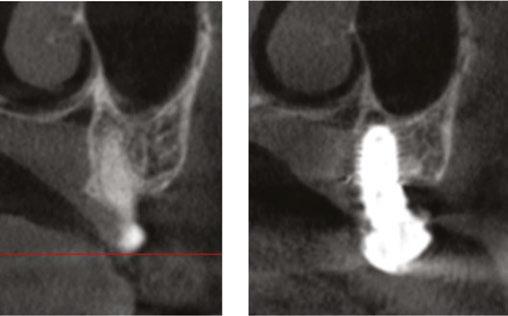

A recent 2025 retrospective review by Holtzclaw, et al.,11 evaluated anonymized cone beam computer tomography (CBCT) scans from 300 sequential referrals using PLACATE guidelines to determine transnasal dental implant feasibility. In this study, inferior conchae were initially located in the coronal plane, and imaging crosshairs were positioned just superior to this structure in the axial plane. To evaluate the ipsilateral and contralateral transnasal engagement points, imaging crosshairs were next positioned over each concha in the sagittal plane. This prelacrimal engagement point, sometimes referred to as the “Z-Point”,6,12 was then evaluated according to PLACATE guidelines as follows:

1. Simmen classification19 determined by measurement from the external aspect of the frontal maxilla to the most anterior aspect of the nasolacrimal canal (Figure 5)

2. Mediolateral measurement of prelacrimal bone width (Figure 6)

3. Vertical measurement of subnasal bone height

4. Vertical measurement from subnasal bone to prelacrimal bone engagement point (Figure 7)

Due to the atrophic nature of the maxilla, treatment following the PATZi protocol was planned.6,17,20 CBCT evaluation revealed pterygomaxillary bone appropriate for pterygoid implants allowing for posterior arch support and cantilever elimination. The zygomas were of adequate height and width to accommodate multiple zygomatic implant fixtures bilaterally. PLACATE guidelines were used to evaluate the patient for potential treatment with transnasal implants. With Simmen 3 nasolacrimal canal classification, ≥ 3 mm of prelacrimal bone, ≥2 mm subnasal bone, and ≤ 25 mm to the Z-point, the patient satisfied all PLACATE parameters. Accordingly, a treatment plan of bilateral pterygoid, single zygomatic, and transnasal implants was agreed upon.